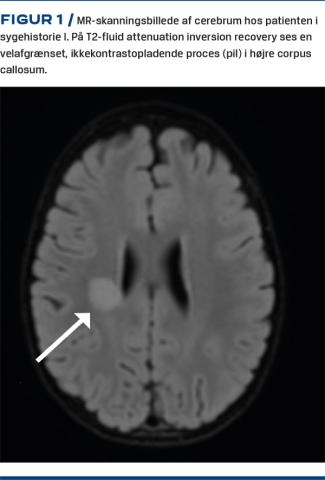

I. En etårig dreng blev indlagt med skelen, feber og opkastning. En uge forinden havde han haft febril luftvejsinfektion, men var restitueret. Objektivt fandtes han at være træt, men ved fuld bevidsthed. Der var skelen pga. venstresidig abducensparese, diskret ataktisk gang, men bevarede dybe senereflekser. Ved lumbalpunktur fandtes mononukleær pleocytose (71 × 106/l leukocytter, 65 monocytære) og normale niveauer af protein og glukose. En MR-skanning af cerebrum viste en 17 × 16 mm velafgrænset, ikkekontrastopladende højsignalforandring i højre del af corpus callosum (Figur 1). Tilstanden blev tolket som mulig viral meningitis eller akut dissemineret encefalomyelitis. Han blev behandlet med ceftriaxon, aciclovir og methylprednisolon.I løbet af fire dage udviklede han slap parese af venstre overekstremitet (OE) og underekstremitet (UE), svær kraftnedsættelse af højre OE og UE samt manglende truncuskontrol. Senereflekserne forsvandt, men abducensparesen bedredes. Drengens perifere sensibilitet var bevaret, og der var udtalte ekstremitetssmerter ved taktil stimulation.Fem døgns behandling med højdosismethylprednisolon og 2 g/kg intravenøst givet immunglobulin var uden effekt. Ni døgn senere fandtes en svælgpodning at være positiv for EV-D68 og adenovirus. Efter påbegyndelse af plasmaferese genvandt han trunkal kontrol og havde langsom motorisk fremgang. Han blev ekstensivt udredt: Cerebrospinalvæsken (CSV) blev fundet polymerasekædereaktions- og dyrkningsnegativ for bakterier og virus, inkl. EV og adenovirus. CSV-flowcytometri, test for autoantistoffer og Borreliaintratekaltest var negative. Fæces EV var ligeledes negativ. En elektrofysiologisk undersøgelse dag 17 var forenelig med akut motorisk aksonal neuropati uden sikre tegn på demyelinisering. Affektion af forhornscellerne kunne ikke udelukkes.Tilstanden blev foreløbigt tolket som Miller Fishers syndrom og svær Guillian-Barrés syndrom, forårsaget af EV-D68.

Vi har beskrevet det første danske tilfælde af AFM/AFP forårsaget af EV-D68. Endvidere er der beskrevet et samtidigt indlagt barn med svær respiratorkrævende luftvejsinfektion forårsaget af EV-D68 og adenovirus. Hos barnet i sygehistorie I var sygdomsforløbet klassisk, idet der først var febril luftvejssygdom, herefter bedring og inden for en uge recidiv af feber og akut udvikling af slap parese. Karakteristisk var også paresernes asymmetri, bevaret sensibilitet og ekstremitetssmerter. Radiologiske forandringer ved EV-associeret AFM/AFP er hyppigst solitære eller multiple, velafgrænsede højsignalforandringer i den grå substans i spinalkanalen, men i litteraturen findes beskrivelser af forandringer i hele centralnervesystemet (CNS) [4]. Billedet her adskiller sig således fra det typiske ved forandringen i hvid substans i CNS.